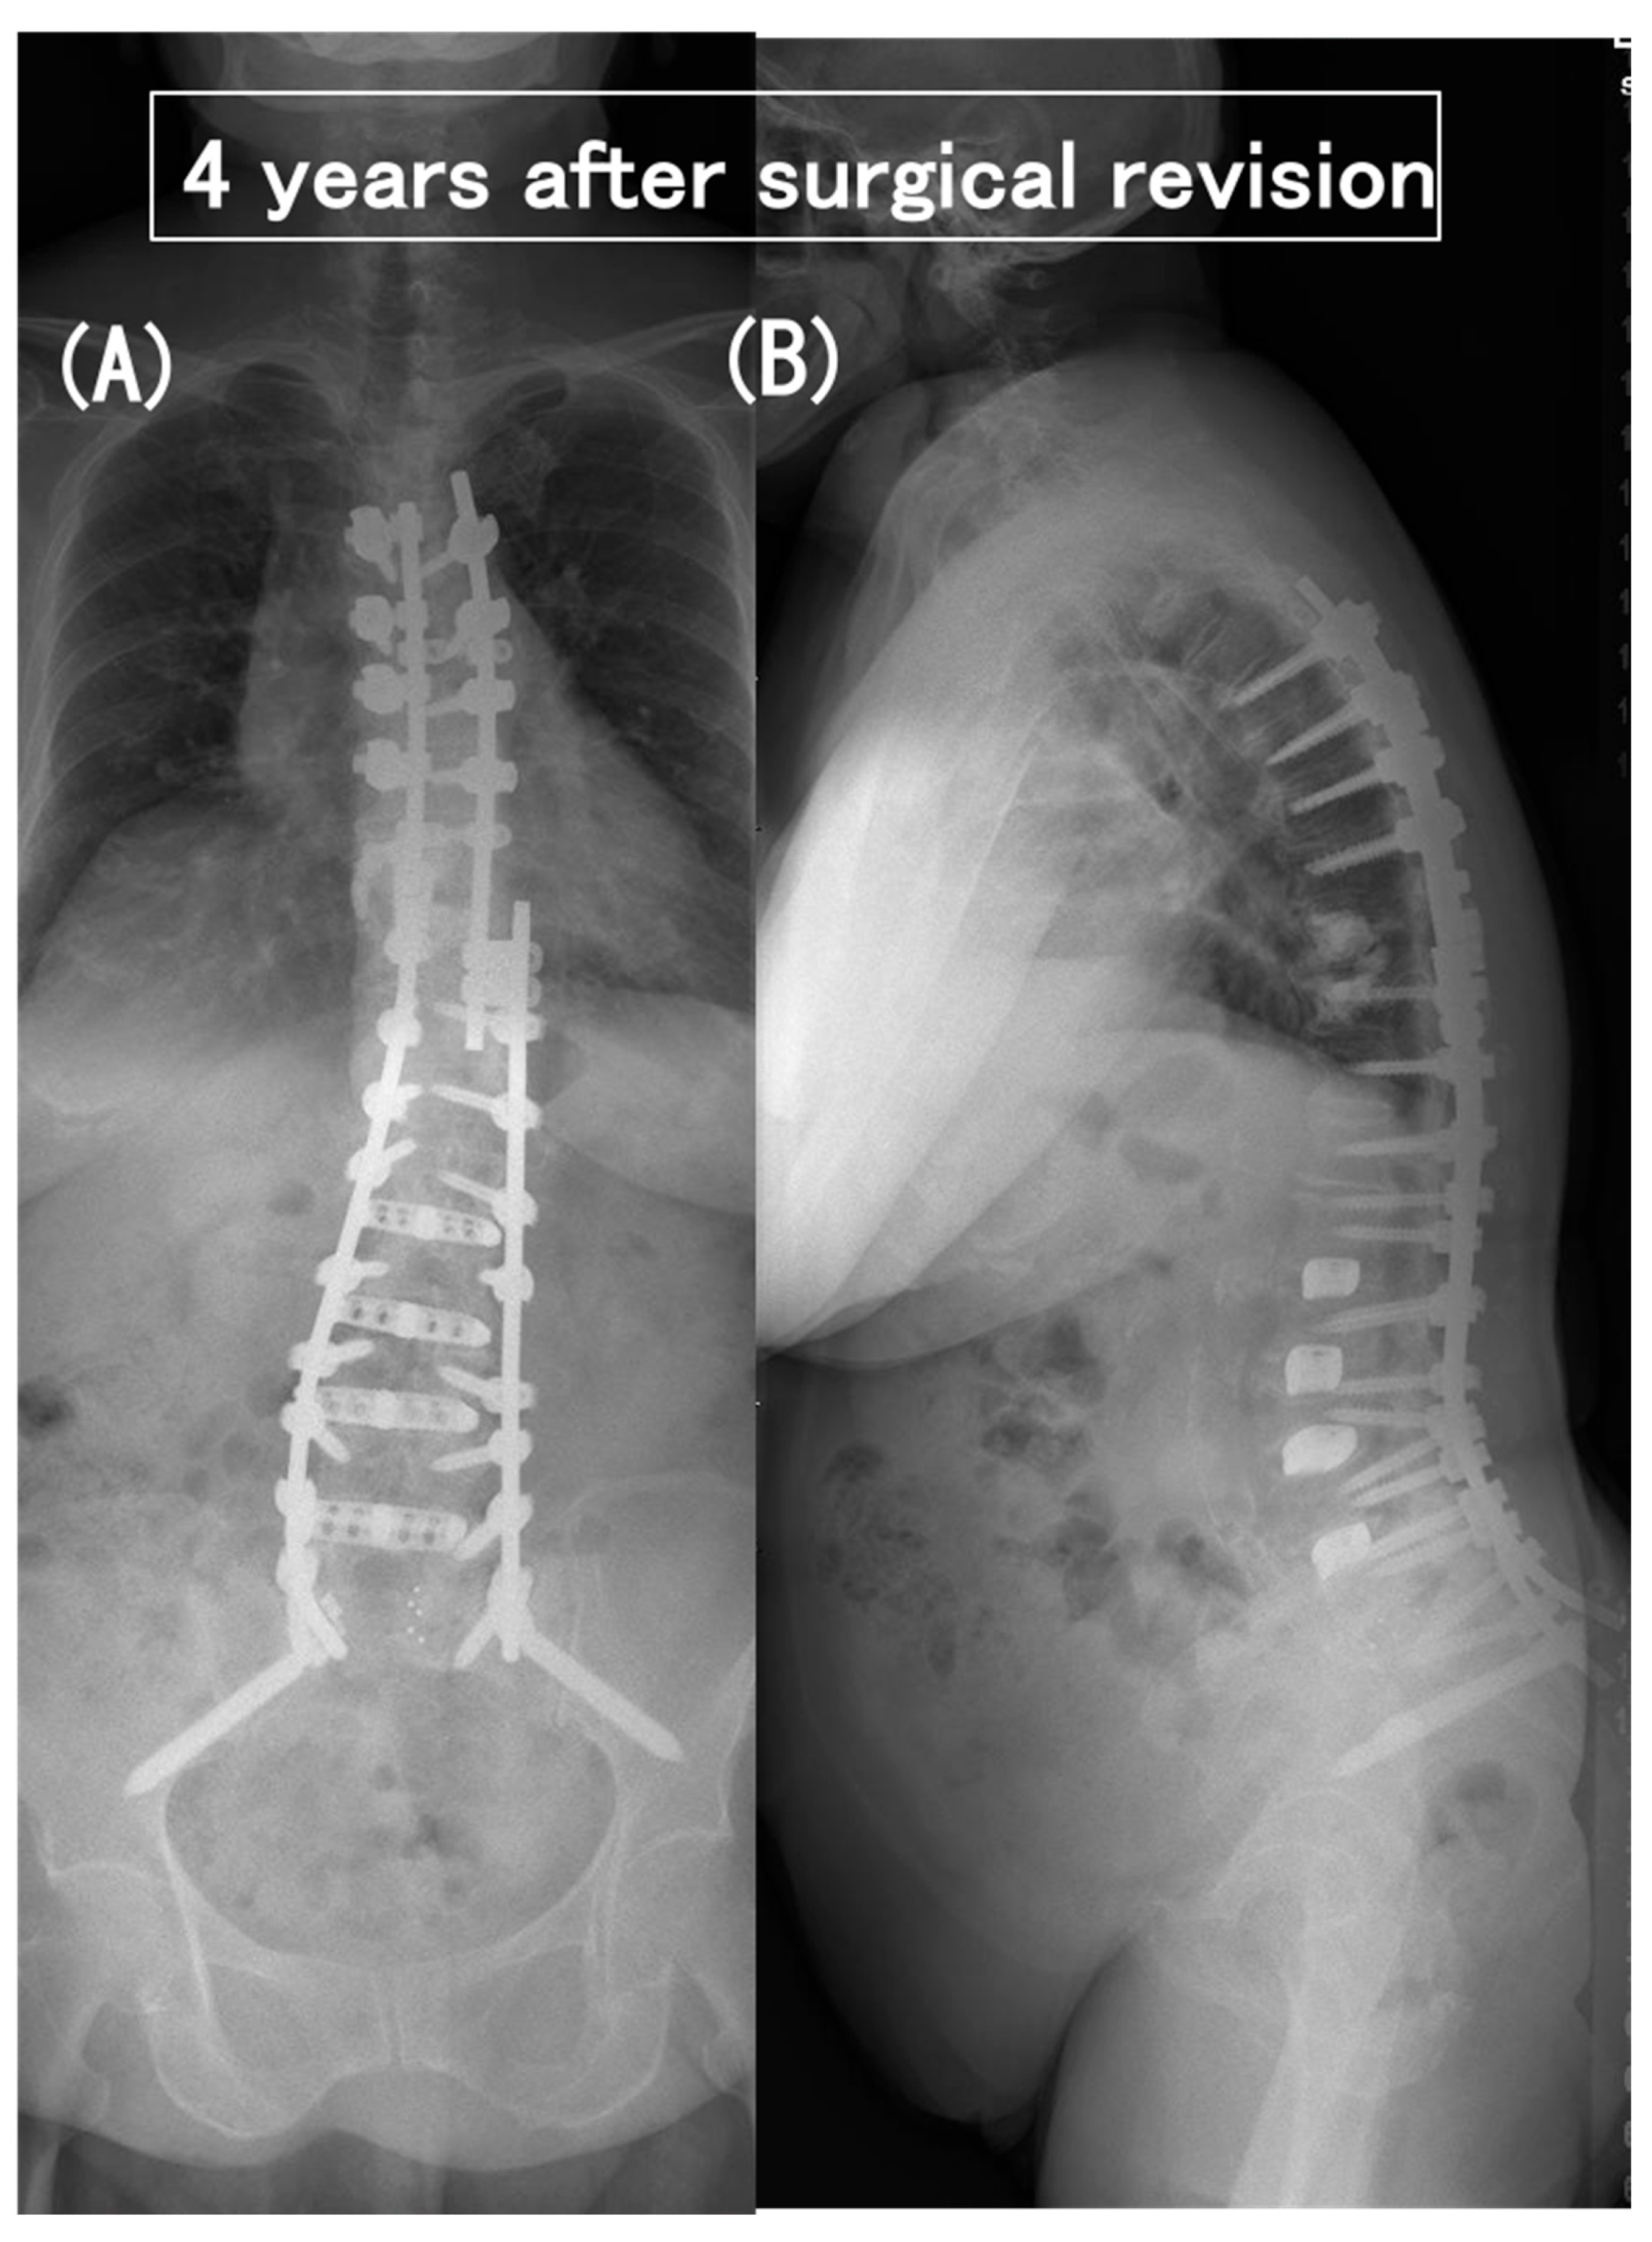

3.6. Case Presentation

- Case no. 6

- 2.

- Case no. 4